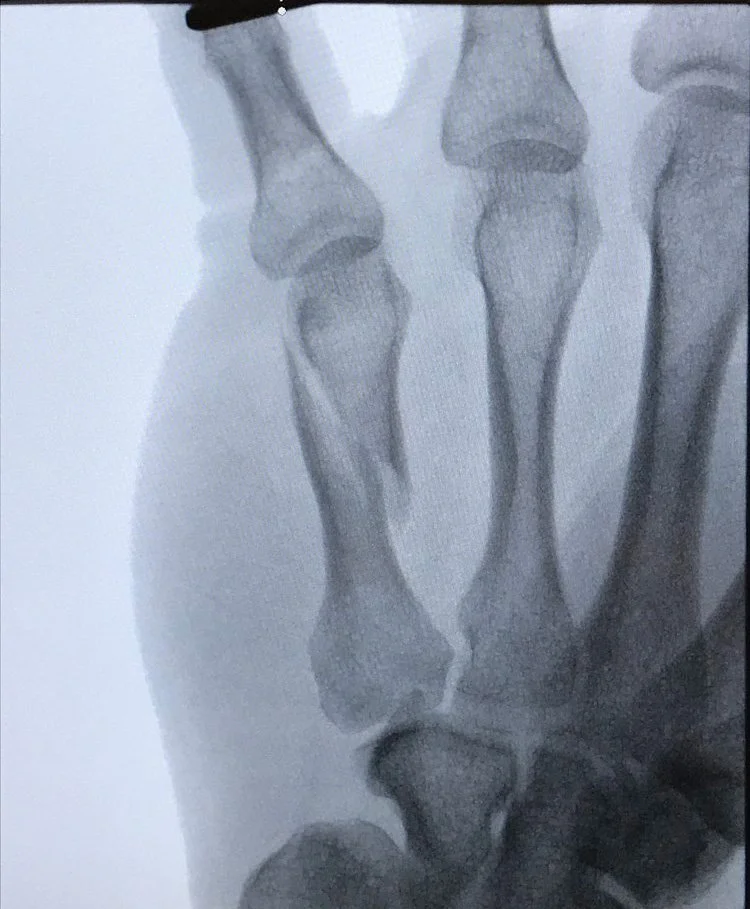

Metacarpal Fracture